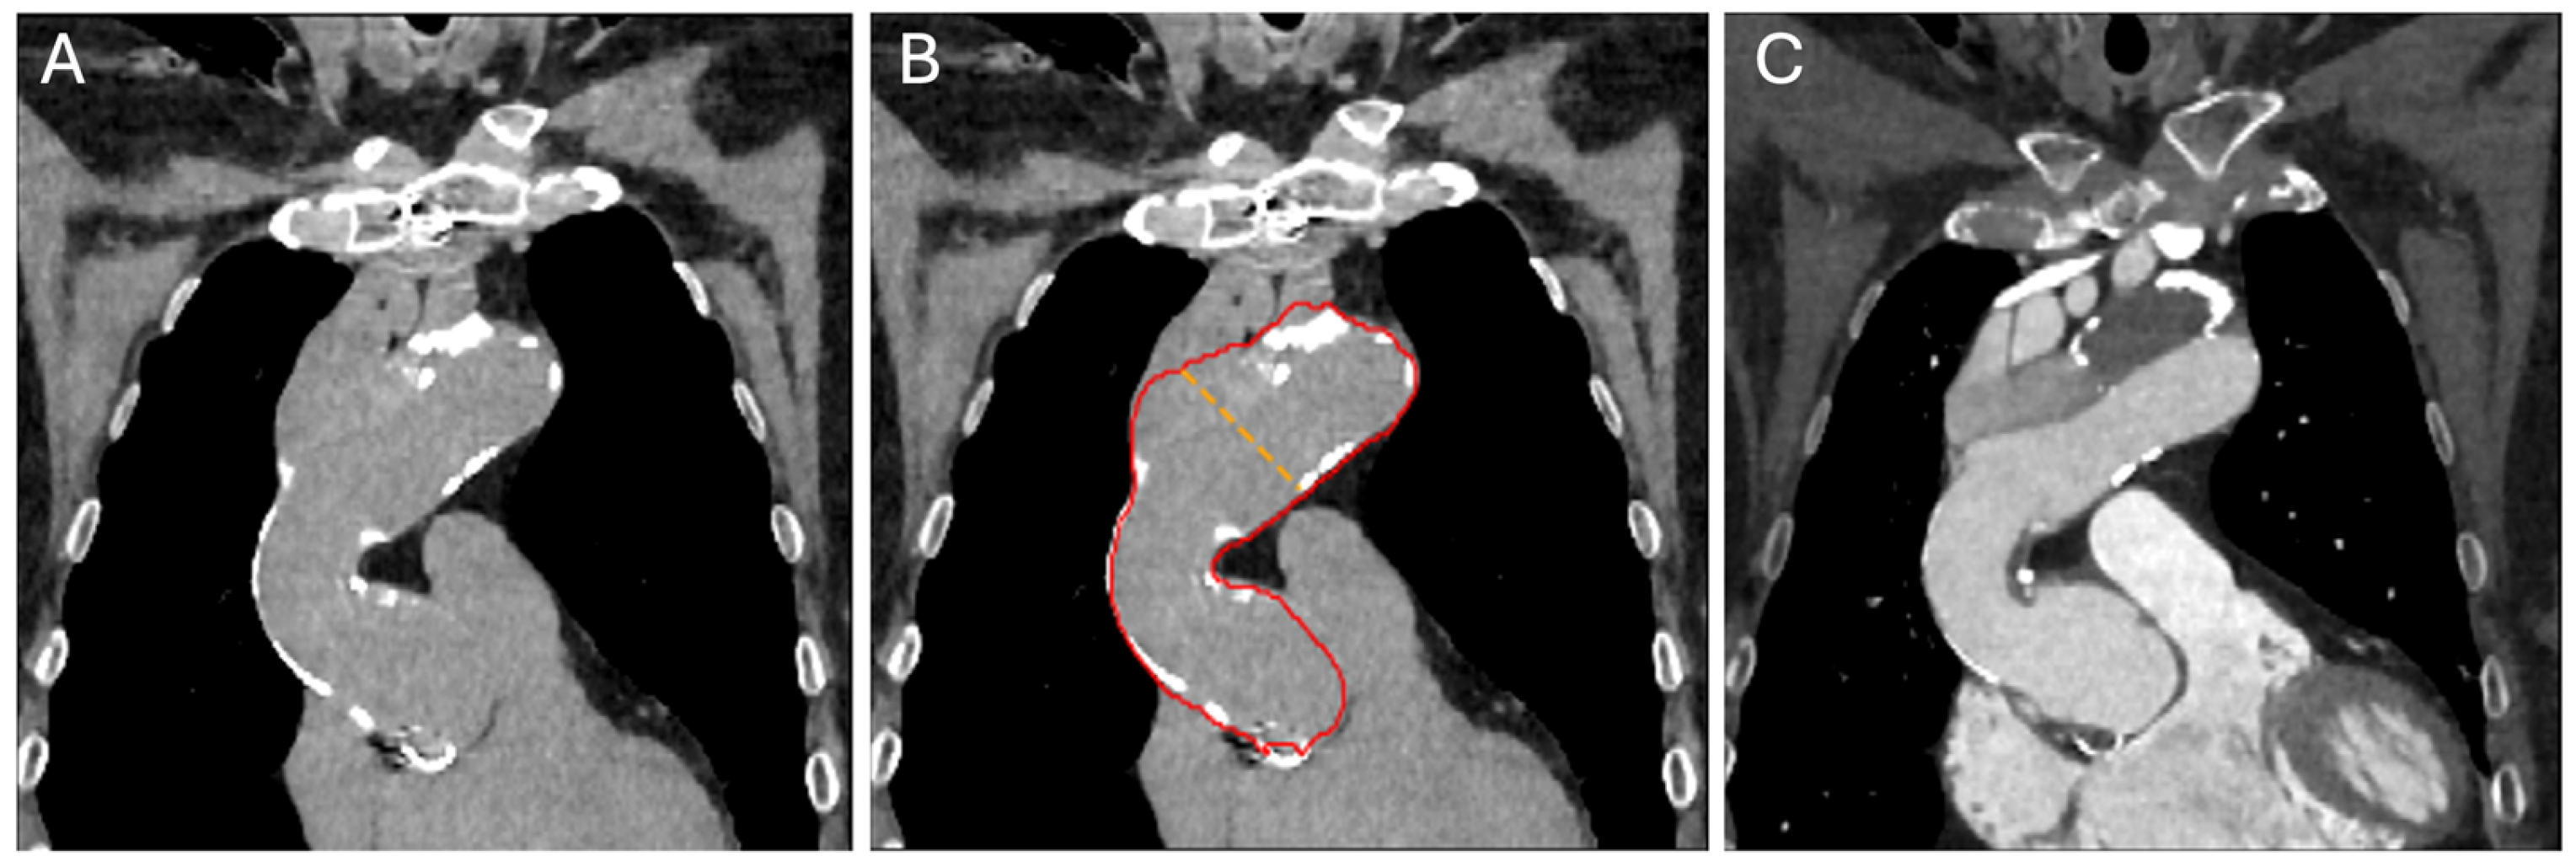

2.3. Convolutional Neural Network Model and Measurements

3.7. DNN-Based Detection of Aortic Dissection